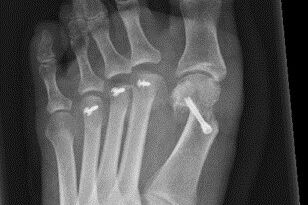

Therapie: distale Umstellung am MT1, Osteotomie an MT 2-4

Die operative Korrektur, bei der Umstellungsosteotomien an den Mittelfußknochen 1-4 links durchgeführt wurden, erfolgte im Mai 2018.

Bei anhaltenden Beschwerden wurde im Mai 2019 eine Röntgenaufnahme durchgeführt, die einen Schraubenüberstand von 1mm am Köpfchen des MT3 ergab. Dieser Befund wurde durch eine CT Untersuchung, bei der zusätzlich eine Arthrose im Grundgelenk der Großzehe und der zweiten Zehe gefunden wurde,  bestätigt.